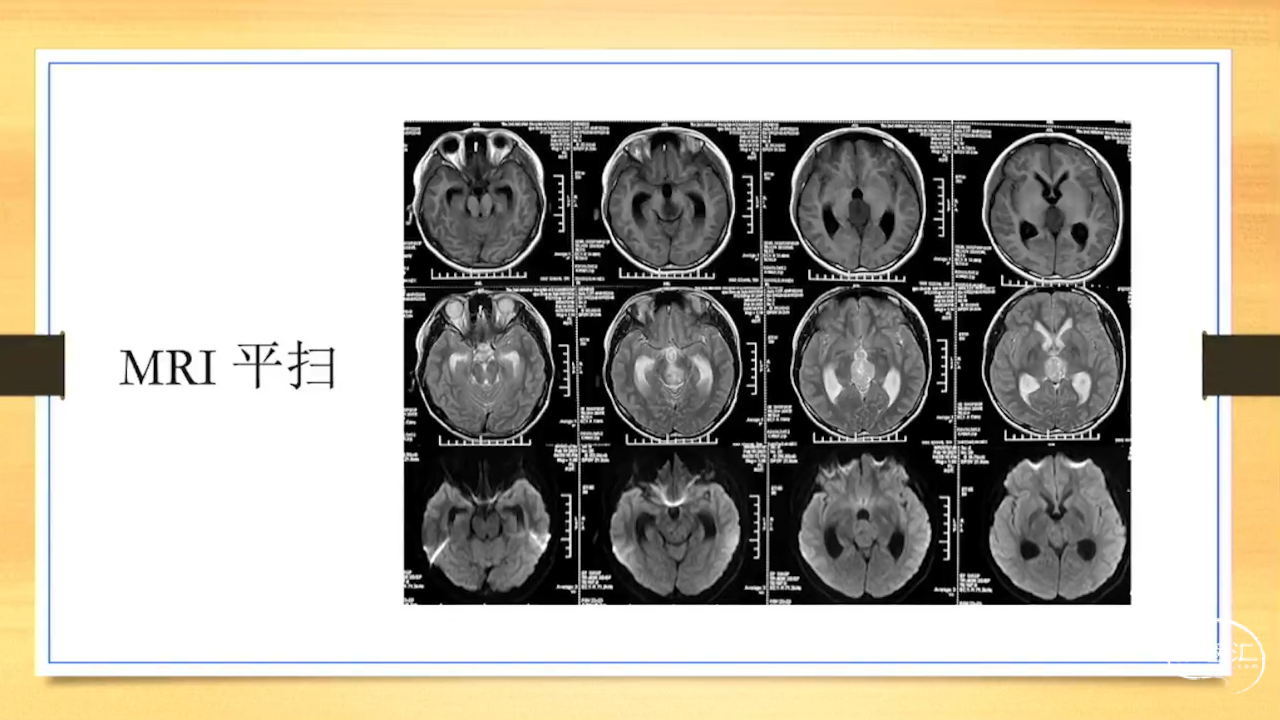

张荣教授:儿童颅内生殖细胞瘤的手术治疗

颅内生殖细胞肿瘤的治疗是手术、放疗、化疗、内分泌及其他多学科的整合治疗。及时、精准、合理的手术治疗是iGCT患者提高生存率、降低并发症、改善神经内分泌功能的关键。